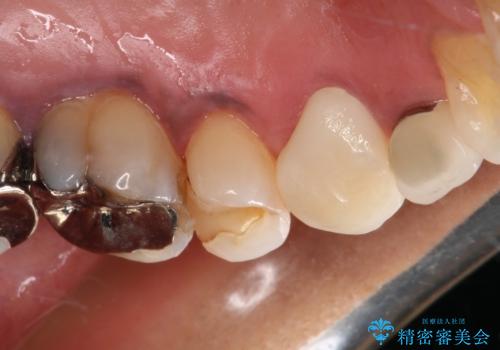

診査の結果、既に歯の神経は失活していたおり、叩いたり触ったりしたときの痛みも確認されました。

まずは根管治療を行い、その後にオールセラミッククラウンにて補綴することとしました。

著しい八重歯であったそうで、一般的に抜歯を行う第一小臼歯ではなく八重歯を抜歯して矯正治療を行ったとのことでした。

補綴治療では歯の形態を犬歯に近づけ、将来的な歯根への負担を軽減できるようにしました。